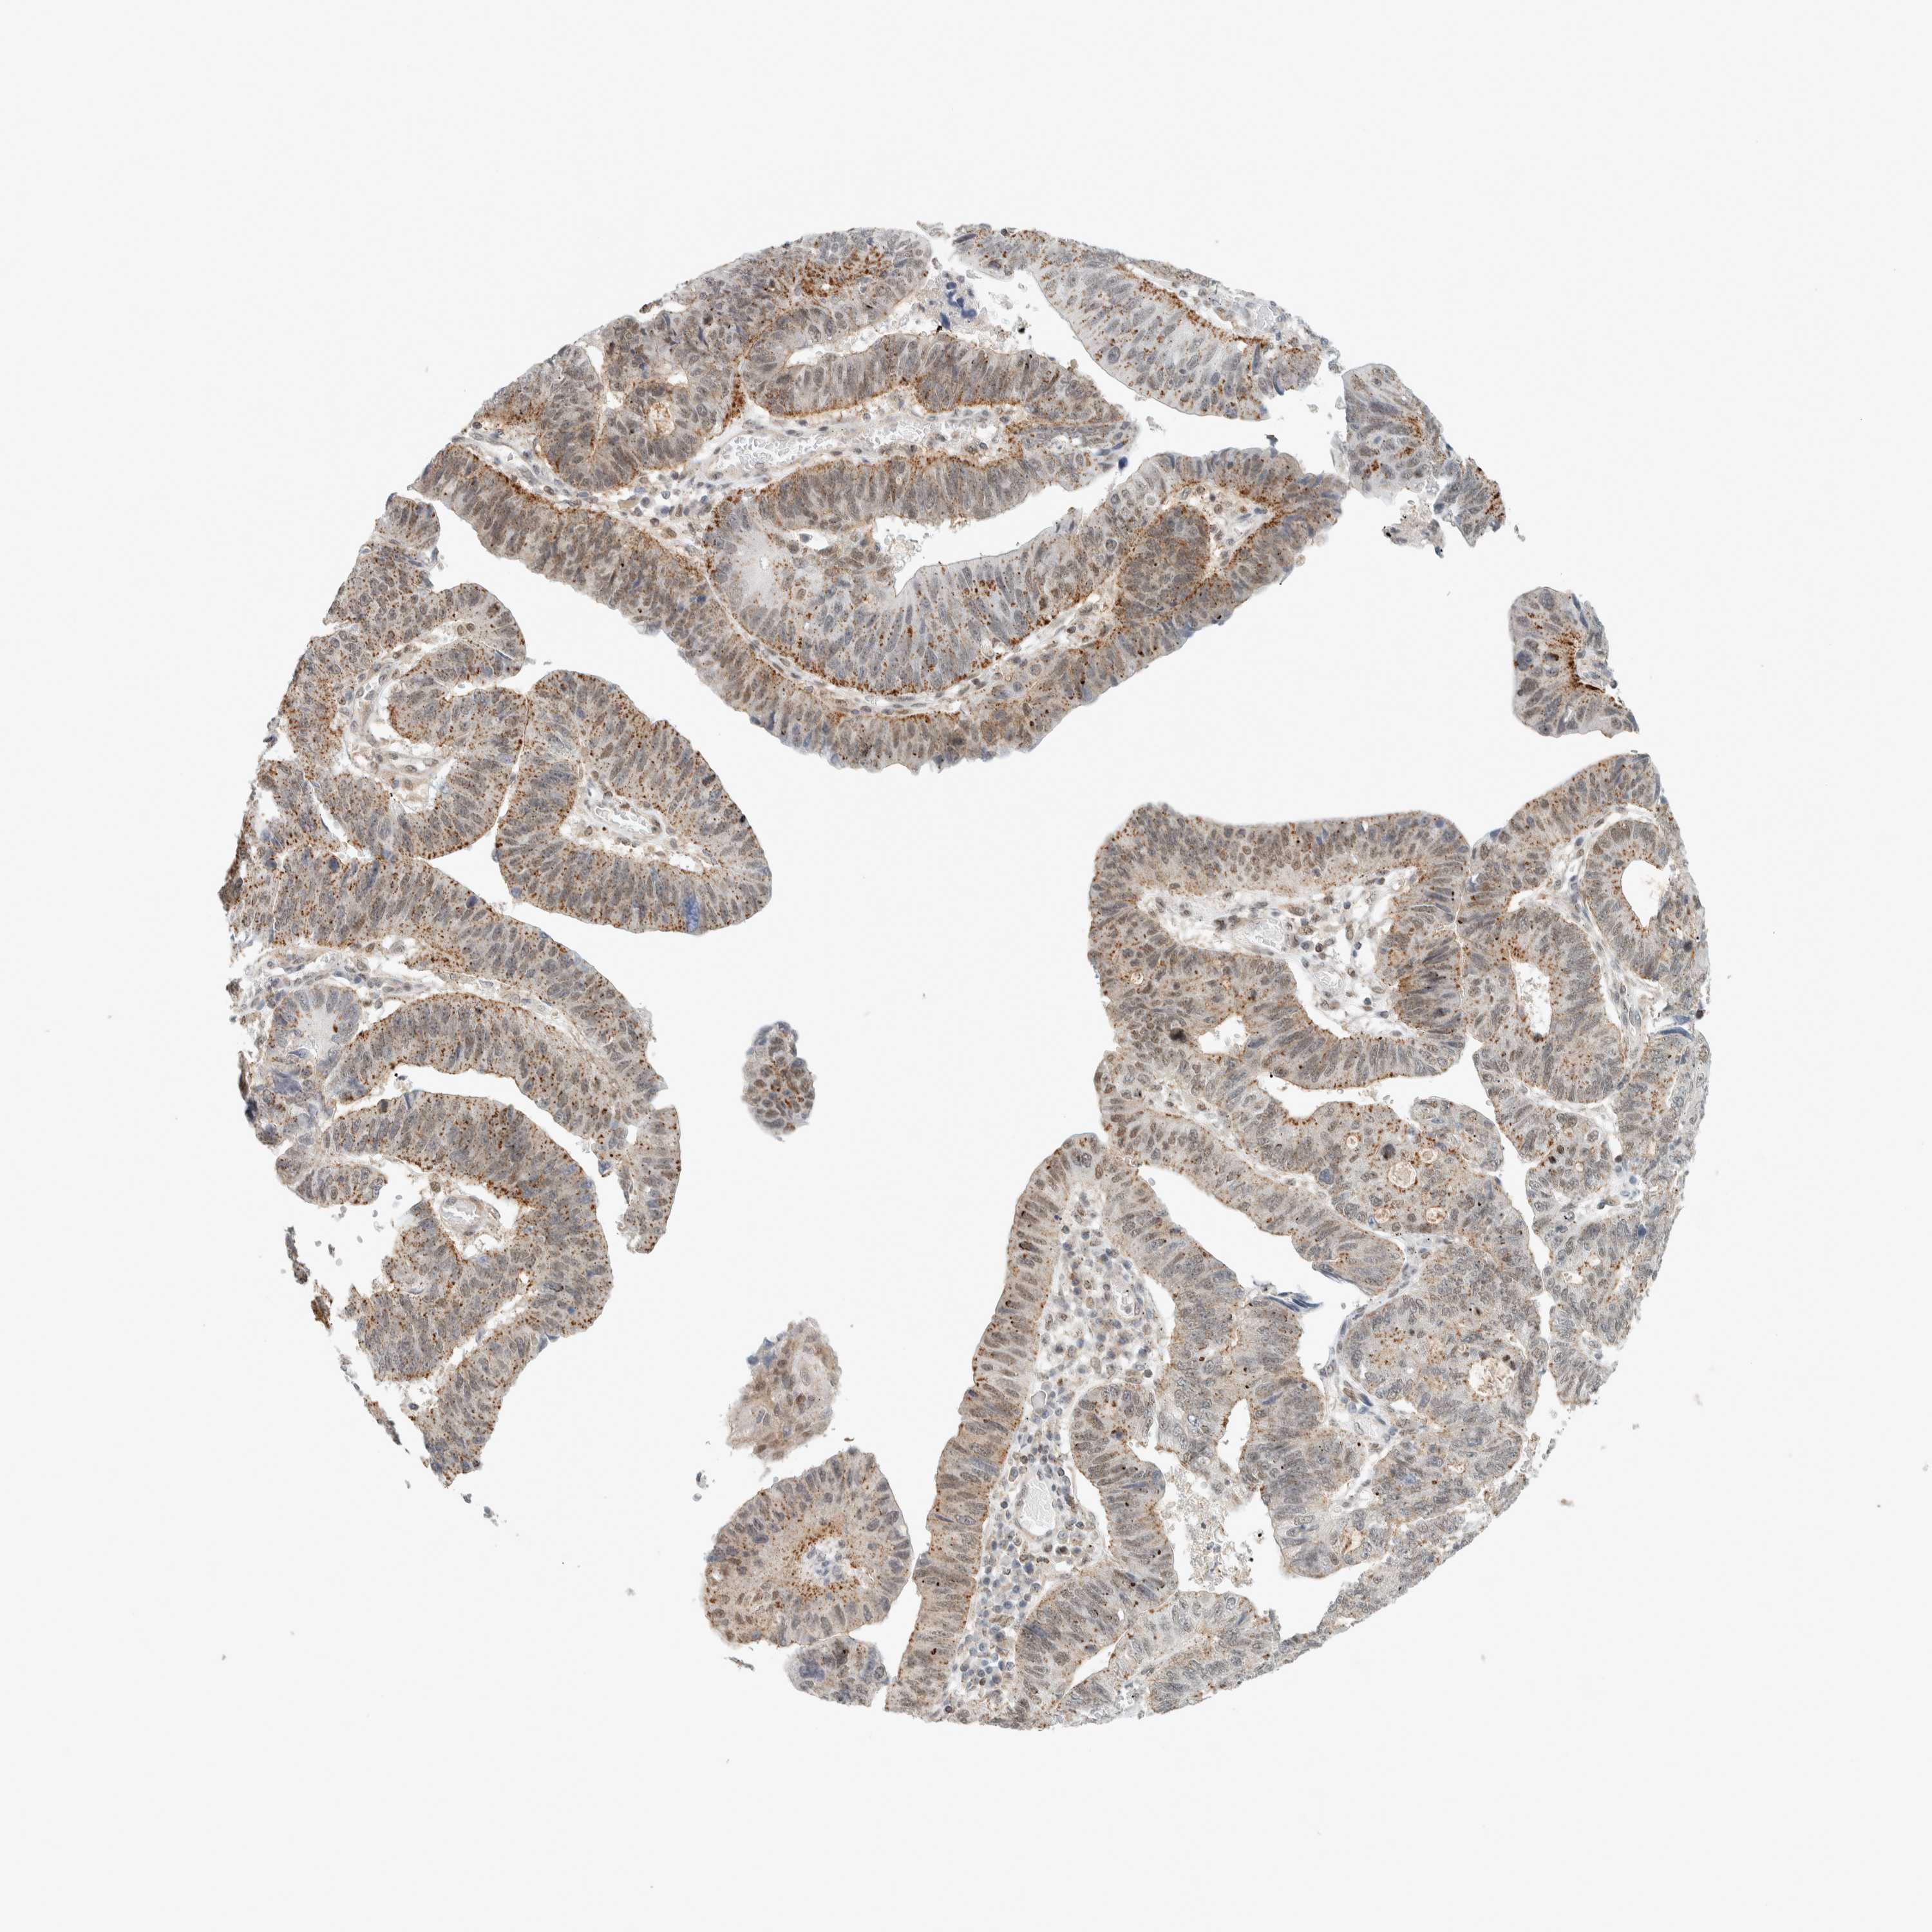

STOMACH CANCER - Protein expressioni

A mouse-over function shows sample information and annotation data. Click on an image to view it in a full screen mode. Samples can be filtered based on level of antibody staining by selecting one or several of the following categories: high, medium, low and not detected. The assay and annotation is described here.

Note that samples used for immunohistochemistry by the Human Protein Atlas do not correspond to samples in the TCGA dataset.

Antibody stainingi

Antibody staining in the annotated cell types in the current human tissue is reported as not detected, low, medium, or high, based on conventional immunohistochemistry profiling in selected tissues. This score is based on the combination of the staining intensity and fraction of stained cells.

Each image is clickable and will lead to virtual microscopy that enables deeper exploration of all samples and also displays staining intensity scores, fraction scores and subcellular localization as well as patient and tissue information for each sample.

Antibody HPA023881

Staining

High

Medium

Low

Not detected

Intensity

Strong

Moderate

Weak

Negative

Quantity

>75%

75%-25%

<25%

None

Location

Nuclear

Cytoplasmic/membranous

Cytoplasmic/membranous,nuclear

Adenocarcinoma, NOS